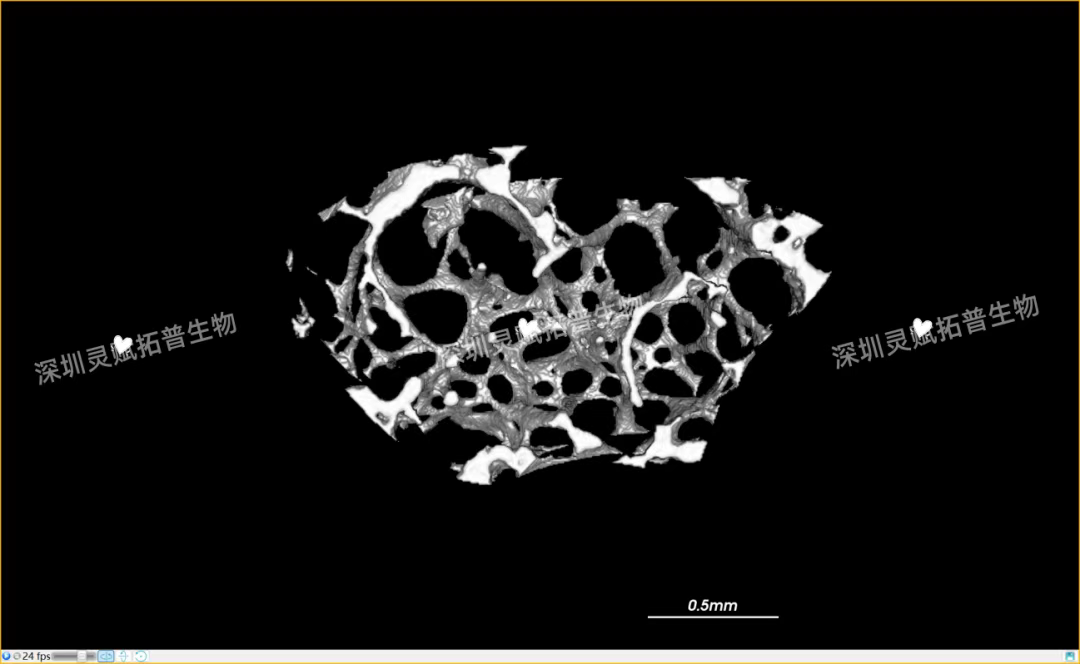

以小鼠股骨检测为代表,带大家直观感受九州ku游官网生物的服务实力:

本次实验对 E2 系列(E2-1、E2-2、E2-3)共3个小鼠股骨样本进行标准化扫描,取得了 0.5mm、2mm 等不同尺度的清晰成像,不仅直观呈现了股骨的宏观形态,更精准捕捉到骨小梁排列、皮质骨厚度等微观细节,为后续骨质疏松、骨修复等相关研究给予了可靠的量化数据支撑。

下附E2系列的典型案例:小鼠股骨扫描成像图